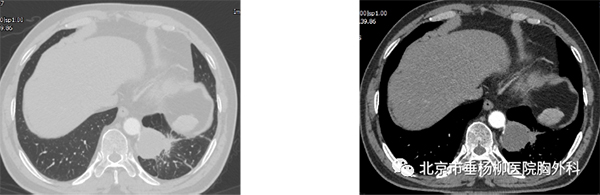

患者男性,60岁,主因“发现左肺下叶占位1月余。以“左肺下叶占位”入院,胸部增强CT:左肺下叶脊柱旁类圆形实性结节影,直径4.5*4.2cm,边界较清晰,增强扫描未见明显强化,可见腹主动脉分支血管进入病灶内。术中叶裂分化不全,左肺下叶与膈肌及纵膈胸膜粘连明显,遂行胸腔镜下左肺下叶切除术,手术历时4小时,完整切除肿物,术后病理回示:叶内型肺隔离症。术后患者恢复良好,术后5天拔出胸腔引流管,术后7天出院。

术前胸部CT(肺窗) 纵膈窗